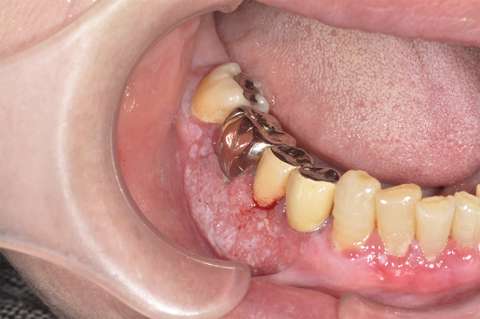

口腔がんの種類

口腔がんが見た目にどのような症状として現れるのか、写真付きでご紹介しています。

症例写真が苦手な方は「写真を表示」をクリックしないようお願いいたします。

進行した下顎歯肉癌の再建の例

顎の骨にまで進行した下顎歯肉癌の術前術後のレントゲン写真です。

切除した顎の骨の部分に、腓骨(足の骨)を移植しています。